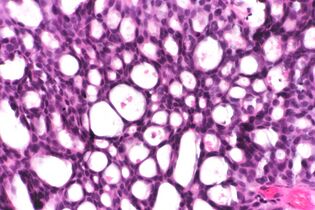

This can be done to slides processed by the chemical fixation or frozen section slides. To see the tissue under a microscope, the sections are stained with one or more pigments. The aim of staining is to reveal cellular components; counterstains are used to provide contrast.

The most commonly used stain in histology is a combination of hematoxylin and eosin (often abbreviated H&E). Hematoxylin is used to stain nuclei blue, while eosin stains the cytoplasm and the extracellular connective tissue matrix of most cells pink. There are hundreds of various other techniques which have been used to selectively stain cells. Other compounds used to color tissue sections include safranin, Oil Red O, congo red, silver salts and artificial dyes. Histochemistry refers to the science of using chemical reactions between laboratory chemicals and components within tissue. A commonly performed histochemical technique is the Perls' Prussian blue reaction, used to demonstrate iron deposits in diseases like Hemochromatosis.[2]